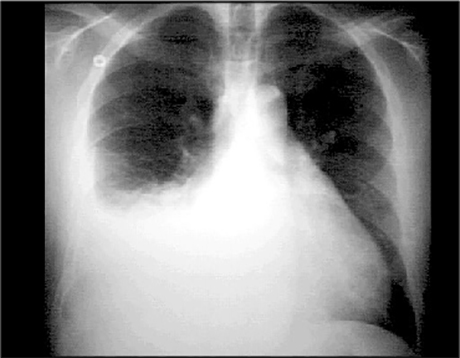

You are incorrect - the best interpretation of the chest X ray in our patient is pulmonary venous congestion.

Your choice: Pleural Effusion PA

This chest X ray shows a pleural effusion. In this PA view, it is demonstrated by a large opaque shadow with a concave upper border that obscures the diaphragm, heart border and half of the lung field on the right side. The left side shows no evidence of effusion. Note the straightening of the left heart border that suggests left atrial enlargement.